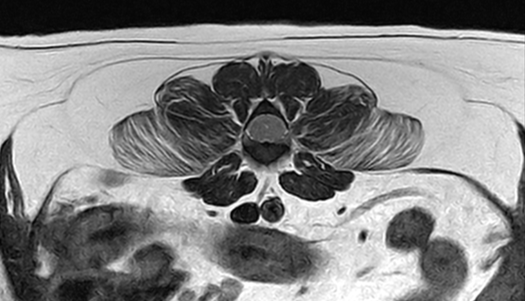

02척추 MRI

· 통증, 마비의 원인 진단

· 척추 실질 질환의 진단

· 추간판 탈출증, 척수공동증, 척수연화증 등

정상 디스크

급성 추간판 탈출증 환자